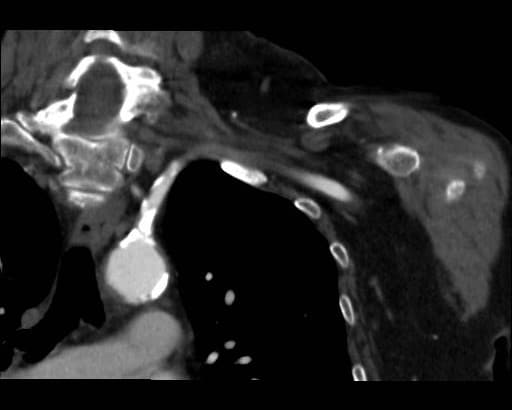

図3.造影CT早期動脈相MIP画像 LAO 45°

図2同様、左鎖骨下動脈起始部は石灰化により高度狭窄が疑われた。